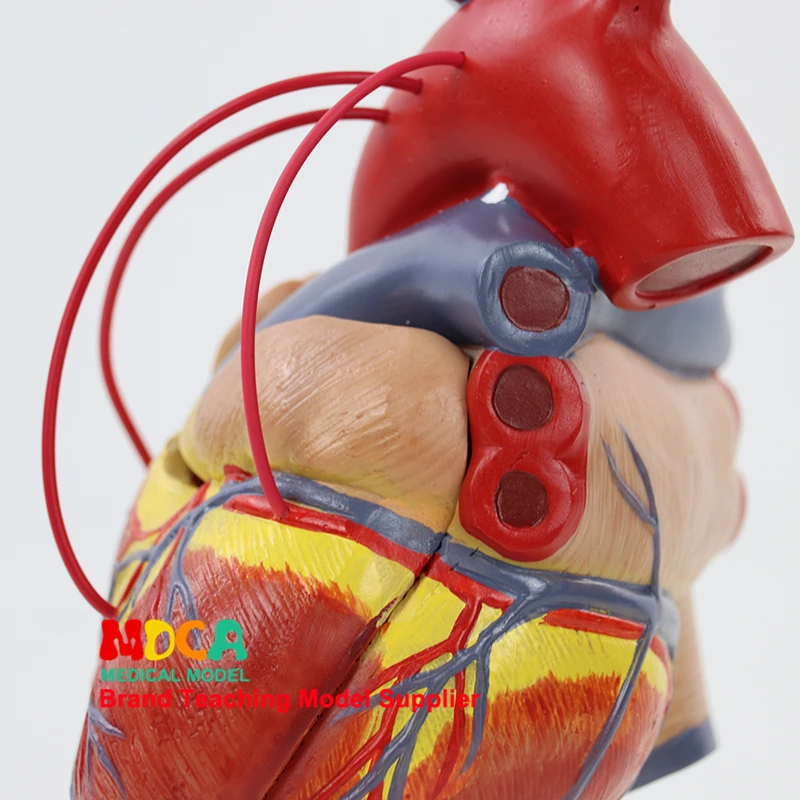

Фотографии и 3D-модели анатомии сердца человека